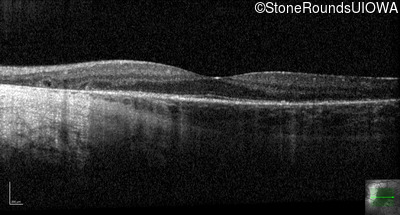

Optical Coherence Tomography - Right - 20/20 -1

Exemplar / OCT Stack

OCT Stack